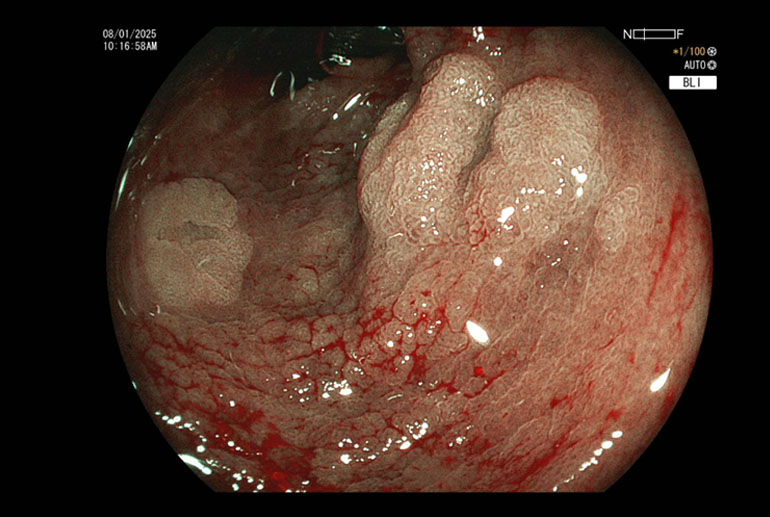

Polyps seen using image enhancement (Blue Light Imaging)Polyps seen using image enhancement (Blue Light Imaging)

Known case of ulcerative colitis for more than 10 years underwent porotocol based surveillance colonoscopy. Multiple flat polyps were encountered in all segments of the colon and a total of 8 polyps were removed using the technique of Underwater Cold Snaring.

Our patient had multiple polyps ranging between 7mm to 15 mm. Most of the polyps were flat, classified as Paris to AA. Several of these polyps were situated in cecum and ascending colon where colonic wall is quite thin and risk of perforation is higher. Using the technique of hydraulic immersion, it was possible to remove all these polyps with minimal risk to the patient. Post polypectomy site of the largest removed polyp was seen to be oozing blood; this was sealed with application of 3 hemoclips; effective hemostasis was achieved and patient did not suffer any complications.